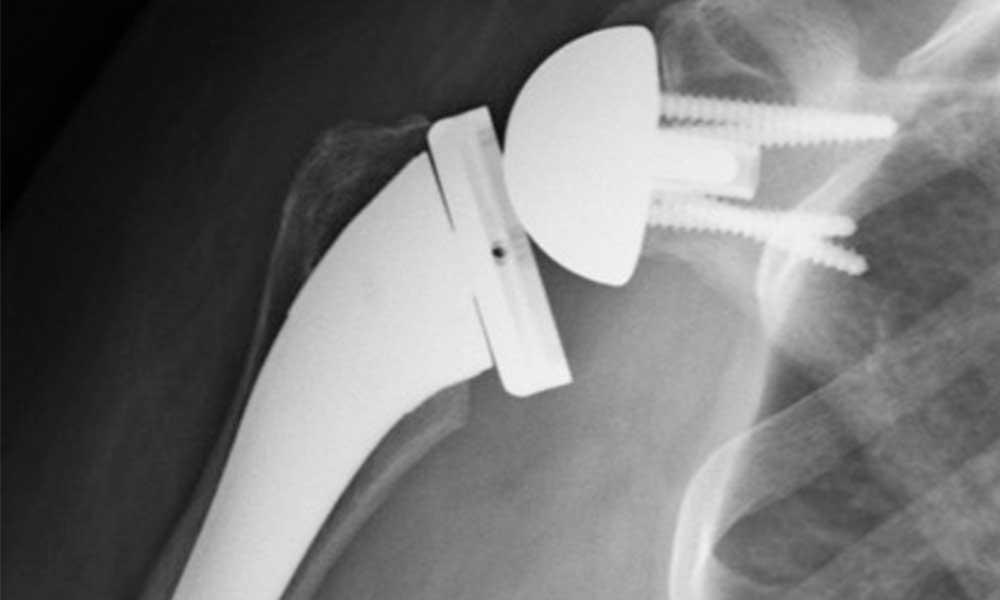

From radiopaedia.org

Reverse shoulder replacement dislocation Image How Difficult Is Shoulder Replacement Full recovery from shoulder replacement can take 4 to 6 months or longer. It’s difficult to say just how long your shoulder replacement will last. How long does total shoulder replacement surgery take? This is usually the result of osteoarthritis, rotator cuff tear arthropathy, avascular. There are many options, ranging from. Anesthesia is usually a general anesthetic although. Are you. How Difficult Is Shoulder Replacement.